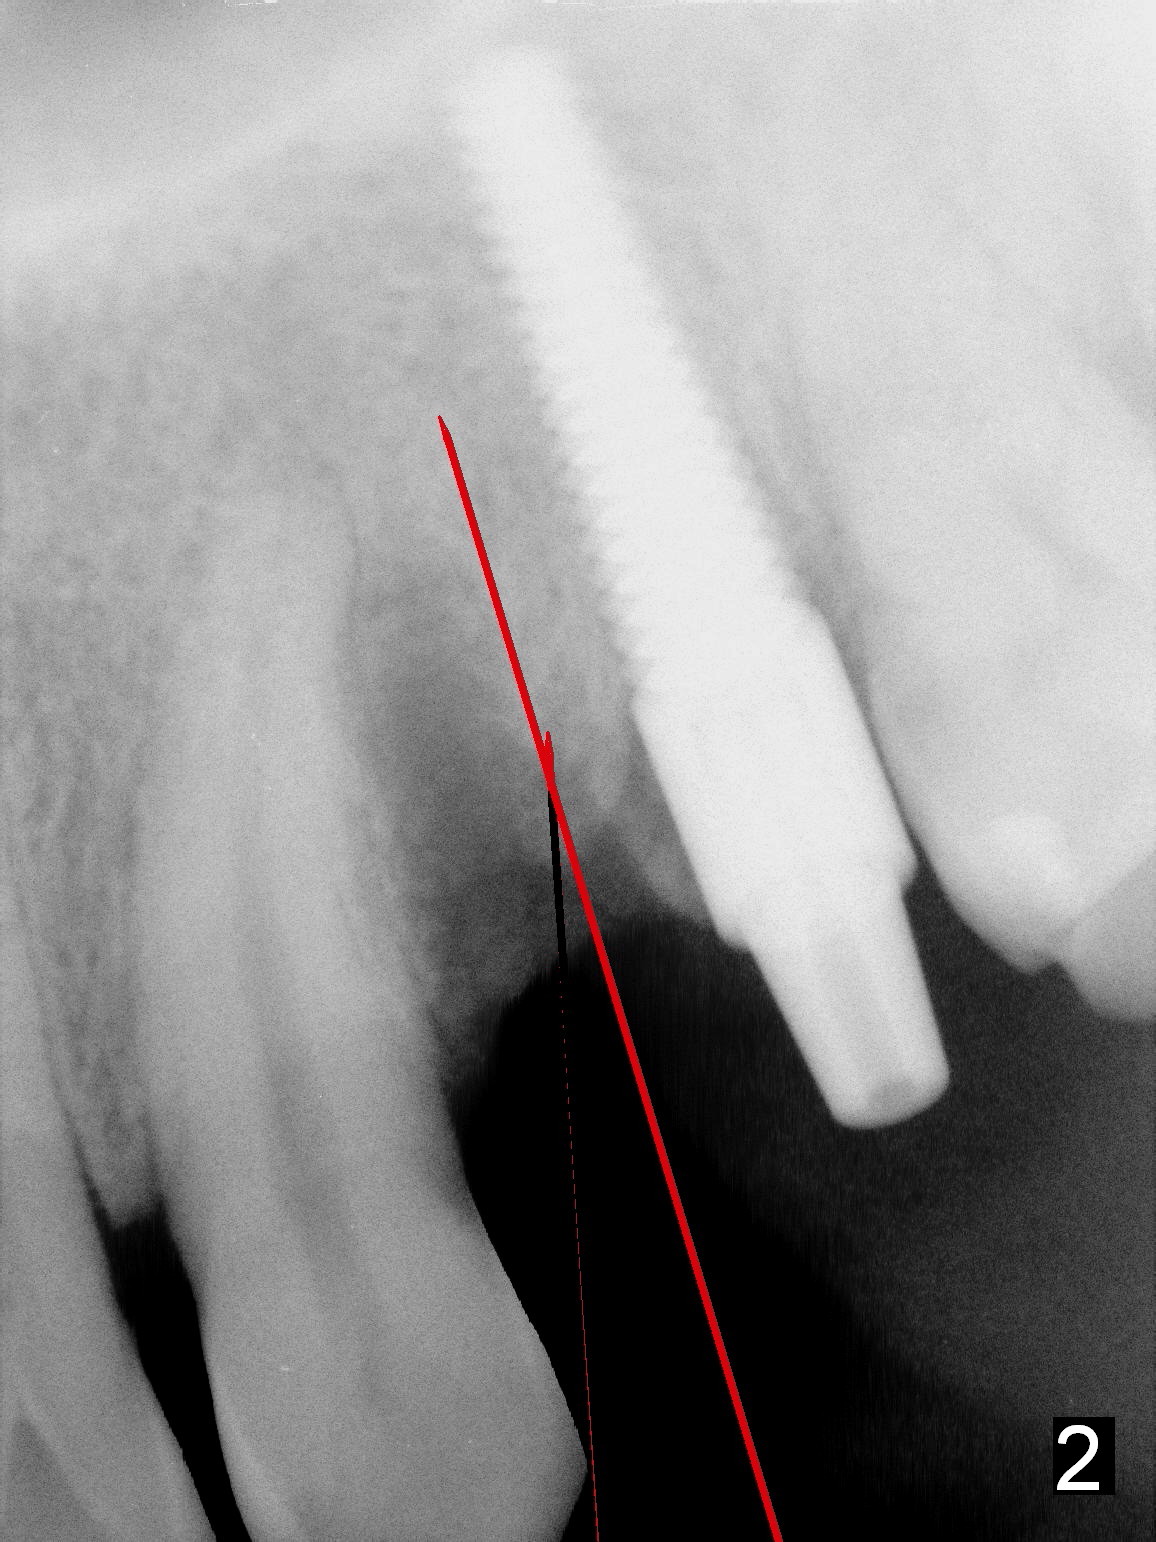

Two and a half months after removal of malpositioned implant at the site of #12 (photos to be taken to show healed socket), a 1.5 mm sharp pilot drill (Tatum, long) will be used (Fig.1 red line) to penetrate the distal slope of the previous osteotomy (photo to be taken). Once the lamina dura is penetrated, the trajectory of the drill is straightened up and deepened until 14 mm from the gingival margin (Fig.2). A 1st intraop PA is taken to confirm the position of the new osteotomy relative to the neighboring structures. If it is correct, deepen the osteotomy until 20 mm (Fig.3) so that it is less likely to be deviated mesially when the diameter of osteotomy is increasing and when an implant (probably 4x20 mm) is being placed. Lean the bur, reamer and implant distally while going deep.